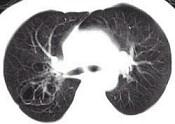

问题 女,23岁,咳嗽咳痰反复发作,根据CT图像,应考虑为 ( )

选项 A.支气管扩张并感染 B.多发肺气囊肿 C.多发性肺囊肿并感染 D.多发性肺脓肿 E.大叶性肺炎

答案 C